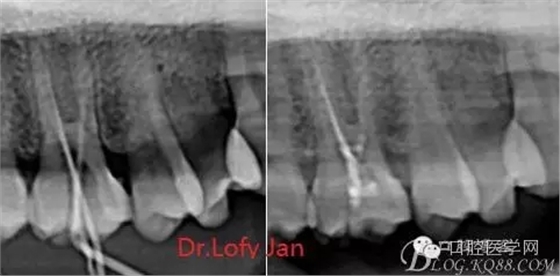

根管治療術(shù)是牙體牙髓疾病治療中最復(fù)雜和最關(guān)鍵的治療項(xiàng)目。根管充填材料抵達(dá)根尖、并能嚴(yán)密堵塞根尖孔,是確保根管治療效果的關(guān)鍵指標(biāo)。為了保證根管充填到位,醫(yī)生需要在術(shù)前照牙片以了解牙根根管的數(shù)量、彎曲程度和長(zhǎng)度,在術(shù)中有時(shí)需要插針照牙片來精確測(cè)量根管長(zhǎng)度,術(shù)后必須照牙片以確定是否根管充填到位,如果欠填或超填,就需要重新充填、重新照牙片確認(rèn),直到根管充填到位。所以,在患者接受根管治療時(shí)有時(shí)會(huì)反復(fù)照牙片。

病例分析:曲面斷層片在x線輔助診斷與檢查中目前大多數(shù)文獻(xiàn)和著作都建議只能作為初診拍片檢查手段,不能作為終末疾病的確診與手術(shù)療效的評(píng)價(jià)指標(biāo),臨床大部分中小型門診都因?yàn)樵O(shè)備不齊全導(dǎo)致信息偏差很大。